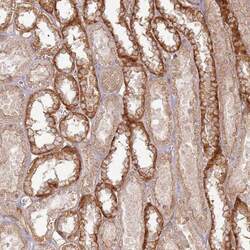

Supportive validation

- Submitted by

- Invitrogen Antibodies (provider)

- Main image

- Experimental details

- Immunohistochemical analysis of ZNF623 in human kidney using ZNF623 Polyclonal Antibody (Product # PA5-60692) shows distinct cytoplasmic positivity in distal tubules.